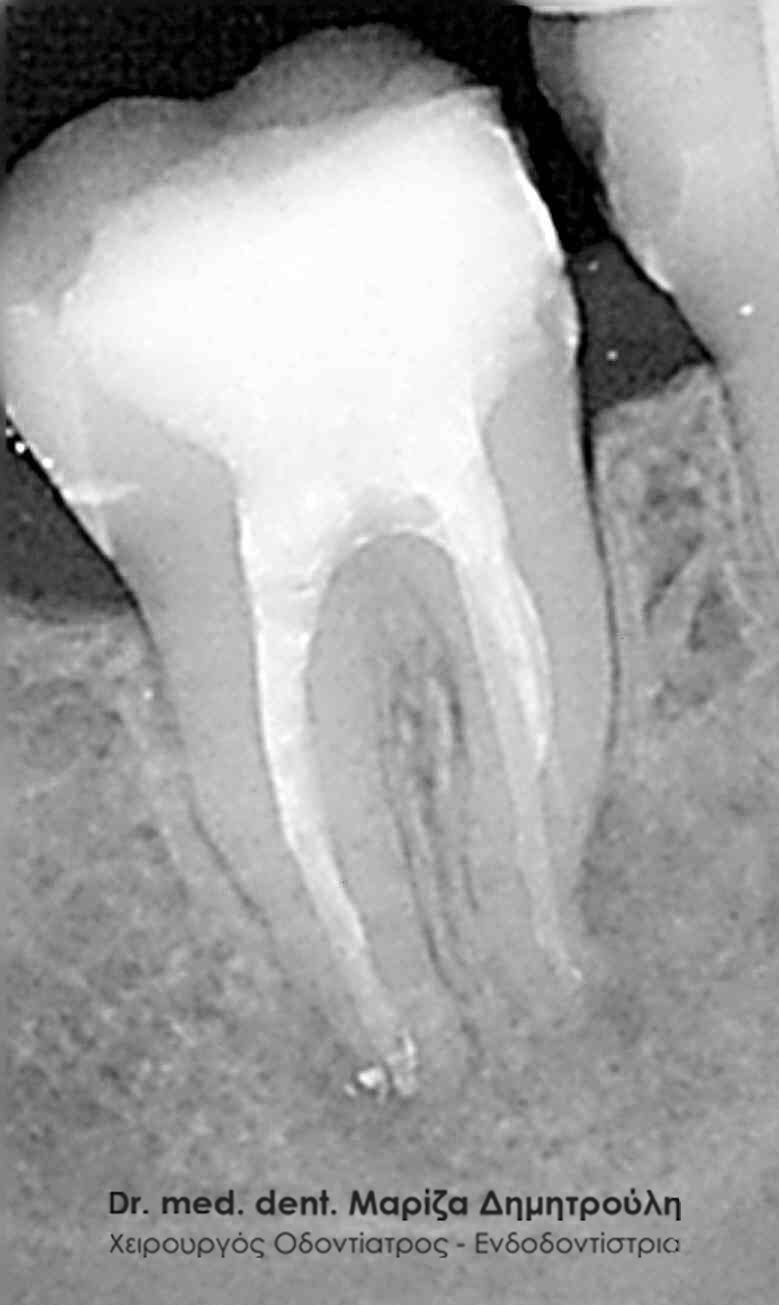

Με την απονεύρωση ο ενδοδοντολόγος αφαιρεί το νεκρό ή μολυσμένο πολφό, όπως και τα νεύρα του δοντιού. Αφού επεξεργαστεί και καθαρίσει πλήρως το δόντι σε 2 ή 3 συνεδρίες,ανάλογα με το βαθμό δυσκολίας του δοντιού, στη συνέχεια εμφράσσονται οι ριζικοί σωλήνες με ένα ειδικό υλικό που λέγεται γουταπέρκα. Σκοπός της έμφραξης των ριζικών σωλήνων είναι η αποφυγή επαναμόλυνσης του πολφού. Στη συνέχεια ακολουθεί η αποκατάσταση του δοντιού με σφράγισμα ή στεφάνη ανάλογα με το έκταση της οδοντικής βλάβης.

Στην περίπτωση αυτή ο ασθενής παραπέμπεται συνήθως στον ενδοδοντολόγο, με σκοπό να ξεκινήσει την επανάληψη της απονεύρωσης. Αυτό σημαίνει ότι ο ενδοδοντιστής θα αφαιρέσει μέσα από τις ρίζες του δοντιού την “παλιά απονεύρωση” ( δηλαδή το υλικό με το οποίο είχαν “γεμίσει” παλιά οι ριζικοί σωλήνες του δοντιού ), θα επεξεργαστεί και θα καθαρίσει εκ νέου τους ριζικούς σωλήνες του δοντιού. Εφόσον το δόντι παραμένει ασυμπτωματικό, η θεραπεία θα ολοκληρωθεί με την έμφραξη τόσο των ριζικών σωλήνων ( με γουταπέρκα, δηλαδή το υλικό με το οποίο εμφράσσονται οι ρίζες των δοντιών κατά την απονεύρωση ) όσο και της μύλης του δοντιού ( με λευκό σφράγισμα ).